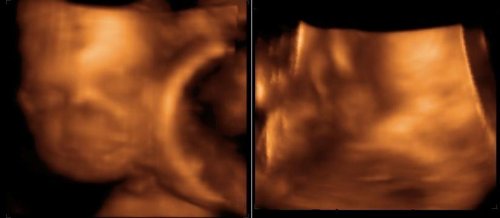

Naše twins 🙂 výbavička